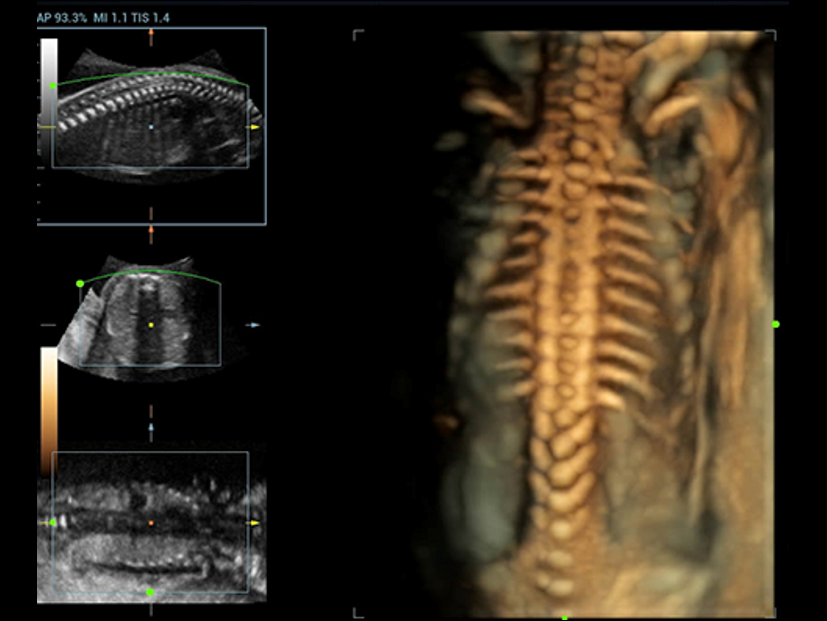

Además de la calidad de imagen de primer nivel, Resona?7 también mejora las capacidades de investigación clínica con el revolucionario V?Flow para la evaluación hemodinámica vascular y con la adquisición de planos más inteligente a partir de conjuntos de datos 3D para el diagnóstico del SNC fetal. Al combinar el funcionamiento multitáctil basado en gestos más intuitivo y todas las características clínicas esenciales, Resona?7 realmente lidera las novedades en innovación de ecografías.